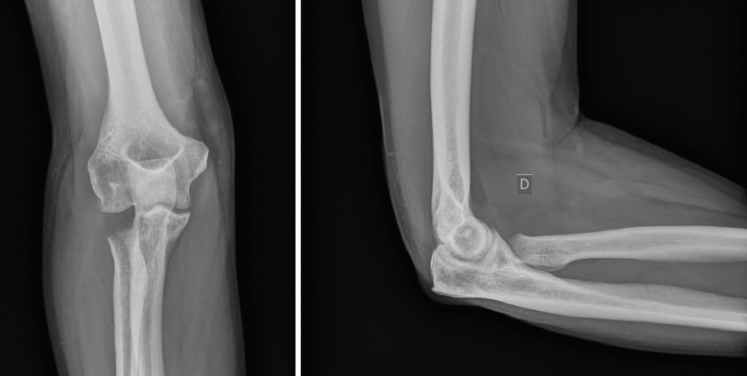

Se solicitarán radiografías simples (Rx) anteroposterior (AP) y lateral. También pueden ayudar las proyecciones oblicuas. En fracturas de la cabeza del radio no desplazadas podemos ver un signo indirecto de hemartros en el perfil estricto, la distensión de las almohadillas grasas anterior y posterior o “signo de la vela” (Figura 1). En casos de inestabilidad asociada podremos ver subluxación de la cabeza del radio respecto al cóndilo humeral. Si hay sospecha de lesión de la membrana interósea solicitaremos Rx posteroanteriores (PA) de ambas muñecas (en posición neutra) y podremos ver variaciones a nivel cubital distal.

Figura 1. Signo de la vela: distensión de las almohadillas grasas anterior y posterior por el hemartros.